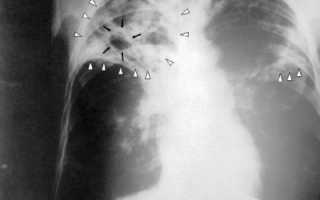

Главный метод диагностики недуга – рентгенография органов грудной клетки. Рентгенологическая картина определяется первичной формой болезни. Если цирротический туберкулез возник на фоне инфильтративной или фиброзно-кавернозной формы туберкулеза, на снимках можно увидеть затемнения различной интенсивности с четкими границами.

Более интенсивно затемнены плотные кальцинированные очаги. Внутри них зачастую обнаруживаются участки светлого цвета, имеющие округлую или овальную форму – бронхоэктазы. В некоторых случаях видно щелевые просветления. Это остаточные каверны.

Также наблюдается утолщение плевры. Остальные участки легочной паренхимы имеют повышенную воздушность, причиной которой является эмфизематозное вздутие. Идентичные изменения обнаруживаются и в здоровом легком.

Если цирротический процесс возник на фоне других форм туберкулеза, локализованных в средней доли легочной ткани, на рентгене можно увидеть «синдром средней доли».

Примерно посредине легкого видно затемнение с четкими контурами. При цирротическом туберкулезе, который развился на фоне диссеминированной формы, участки затемнения определяются в верхней половине обоих легких.

Плеврогенная форма цирроза на рентгене проявляется уменьшением размеров пораженного легкого. Кроме того, на снимке можно увидеть смещение органов средостения в сторону патологического очага и повышение воздушности остальной легочной паренхимы.